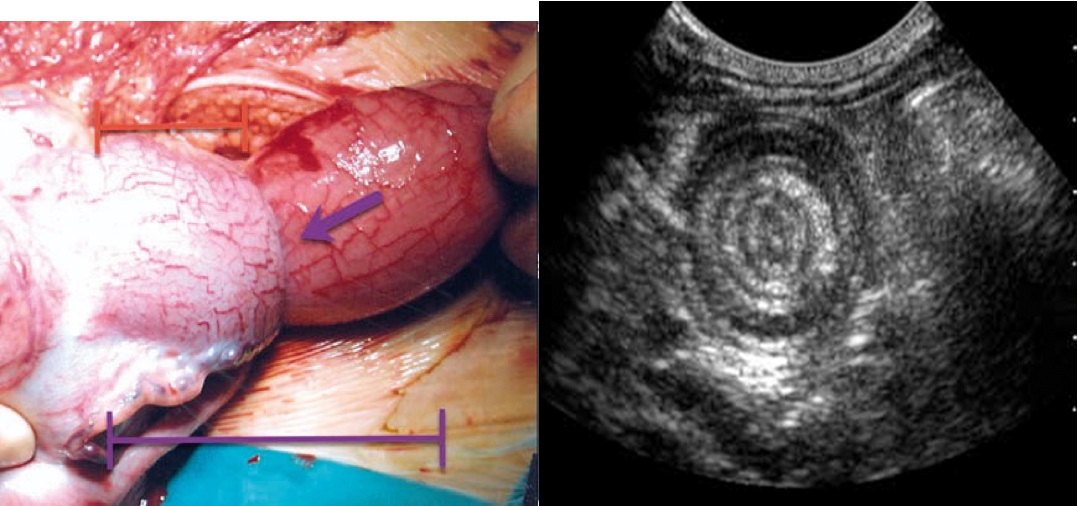

- Is most often ileocolic, less commonly colocolic.

- The upper portion of the bowel, the intussusceptum, into the lower, the intussuscipiens.

- Constriction of the mesentery, obstructs venues return, leading to edema, bleeding (some times necrosis and perforation) from the mucus of the intussusception and causing bloody stool with mucus (Current Jelly stool).

Target sign in intussusception

Ultrasound abdomen (bowel; transverse plane)

Concentric alternating hyperechoic and hypoechoic rings are visible. The hyperechoic rings (green overlay) are formed by mucosa and the hypoechoic rings (red overlay) by submucosa. Together the alternating layers produce a target-like appearance (target sign; bullâs eye sign).